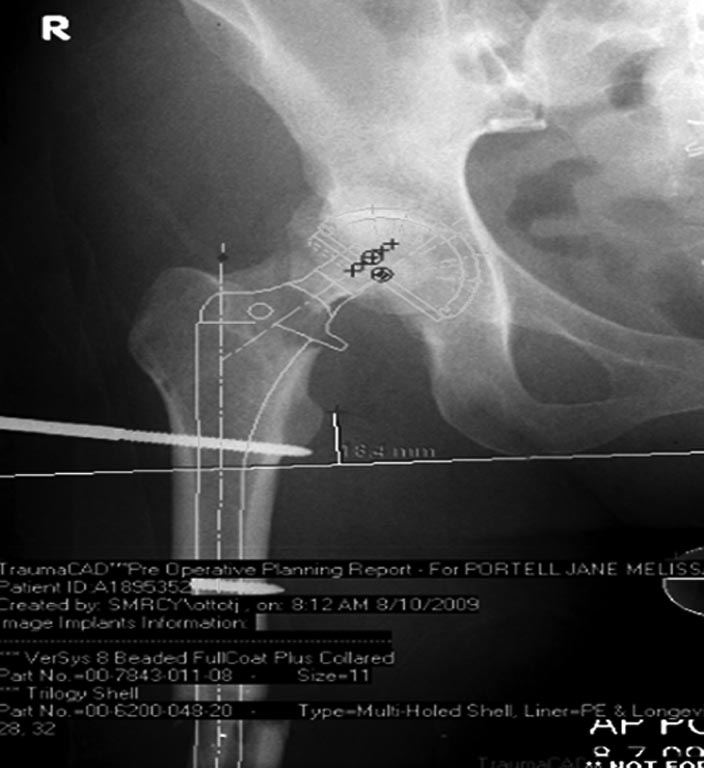

Из вариантов фиксации для проксимального и диафиза бедра выбрали

пластину, а по поводу артропластики остается вопрос между тотальным или

геми.

На всякий случай запланировали: короткий и длинный вариант ножки.